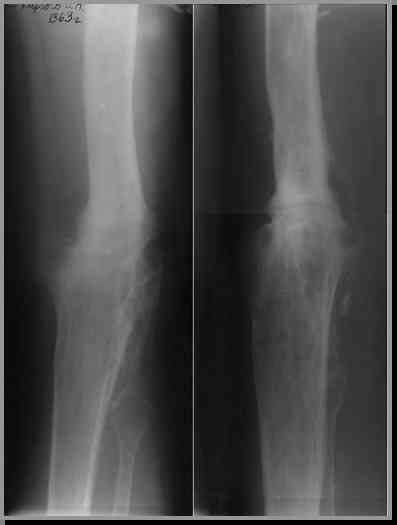

Мы в нашем отделении активно обсуждаем все ваши советы и пока не пришли к окончательному решению, благо пациент будет ложиться в отделение в пятницу 9 февраля, и нас есть еще время подумать и надеемся получить письма и от других коллег. Что касается лично меня, то я пока склоняюсь к более радикальной операции - резекции кости. Но о нашем окончательном решении обязательно сообщу.

Этот стиль мне полностью приемлем и понятен. Наверно я бы поступил также. Но статистика упрямая вещь. Сколько у тебя или у другого врача опыта по замещению дефектов бедра? У меня за 25 лет работы 3, и еще около 15 случаев удлинения бедра. Случай у тебя очень сложный. Если Вы выбираете Илизаровскую методику то надо на в/з хорошую дугу, не менее 4-5 спиц с напайками.Стержни хороши когда кость не измучена и на 2-4 месяца. Здесь аппарат на 6-8 месяцев. Если есть желание я только за, и

Прикрепляю пример замещения дефекта бедра 20 см, после резекции по поводу опухоли, эндопротеза Сиваша, вялотекущего остеомиелита со свищами в течении 3 лет. Получилось хорошо и всего за 6 месяцев в аппарате. Колена не было. У Вас случай сложнее. Это было в 1998г. Я работал в ЦИТО и у меня было 4 больных, я занимался им с утра до ночи. Сейчас 60 больных и операций в нашем отделении 25-30 в неделю.Если могу чем помочь - нет проблем.